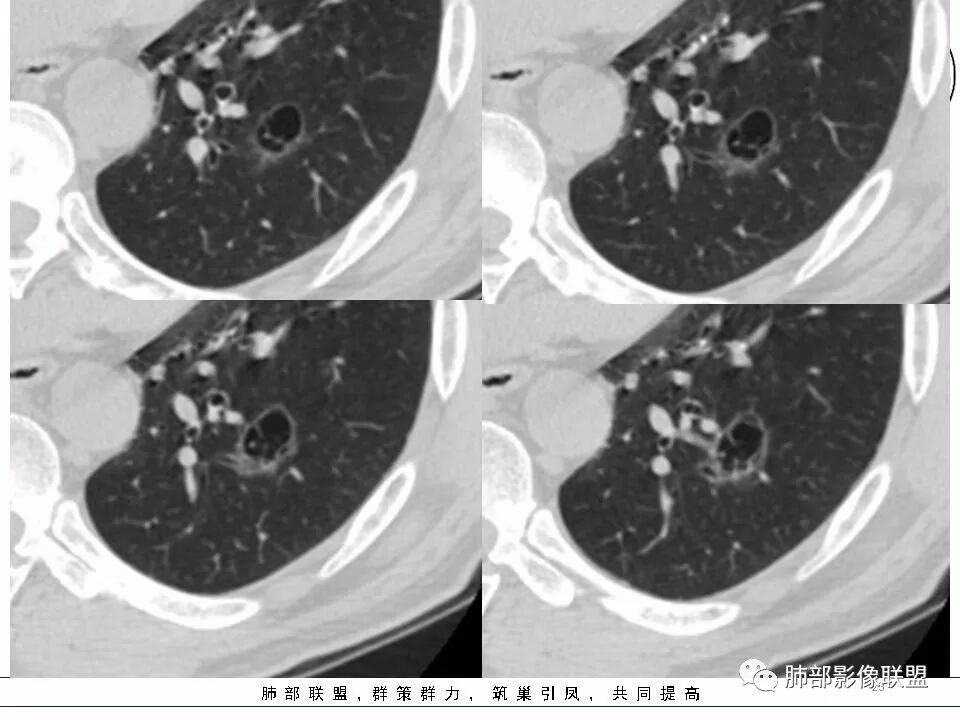

53岁男性,间断发热半月余,肿瘤指标不高。CT:左下肺囊腔样病变,内见分隔及点状线条样影,壁偏心性增厚,下缘血管穿过并增粗,后方伴边缘清晰,磨玻璃影,边缘有轻度膨隆及分叶,支气管未见截断。考虑囊腔型腺癌可能性大。

53岁男性,间断发热半月。胸CT:左下叶囊腔性病变,外形边界不规则,周围有边界较清楚磨玻璃,囊内见分隔,囊壁厚薄不均,壁结节,内有小囊,血管集束。考虑:囊腔样腺癌?鉴别:肺大疱、CPAM、PLCH等。

2.左肺下叶外基底段囊腔样病灶,轮廓柔和,壁厚薄不均,见壁结节。内见分隔或脊状突起。腔内见血管穿行。

这是有“故事”的囊!

3.囊壁外环以磨玻璃影,边界较清楚。

1.囊腔壁厚薄不均,壁结节,内有分隔,其内有血管穿行,指向新生物。

2.临近有边界清楚磨玻璃影,指向腺癌。